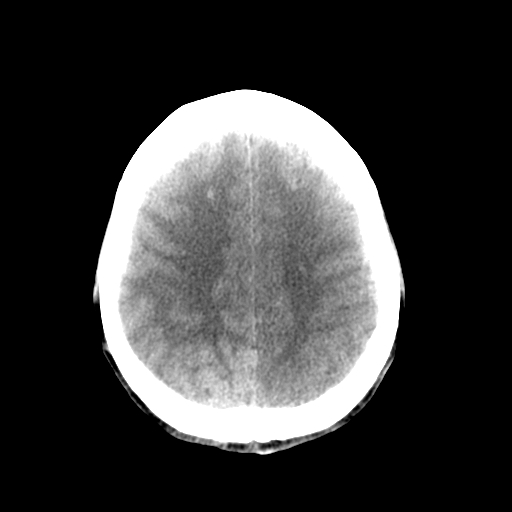

标题: CT17002:M48Y,血管畸形,血管瘤,请鉴赏! [打印本页]

标题: CT17002:M48Y,血管畸形,血管瘤,请鉴赏!

男48y,头痛多年,加重一天!

典型的血管畸形---avm  -----右侧枕顶叶及侧脑室三角区等高混杂密度影夹杂少许低密影显示,无明显水肿,增强可见明显的供血动脉与引流静脉显示